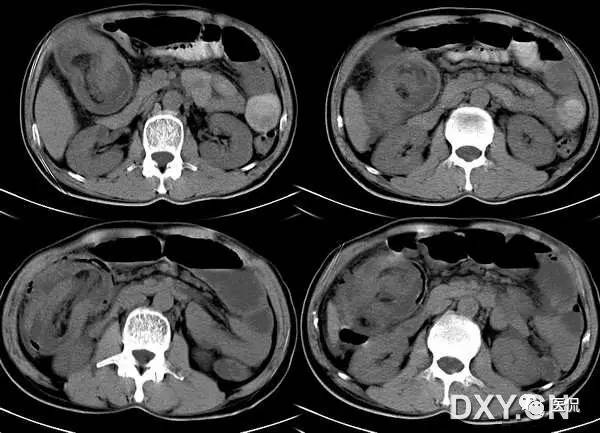

是肠套叠最常见的特征性CT征像,为肠套叠长轴与CT扫描层面垂直时的表现,折射了套叠的各层肠壁、肠腔及肠系膜间的关系。典型排列为自外向内分别代表鞘部外层肠壁、鞘部肠腔内造影剂、鞘部内层肠壁、偏心性套入部肠系膜、套入部肠壁、套入部肠腔内造影剂。:

肠套叠是指一段肠管及与其相连的肠系膜(套入部)被套如其相连的一段长管内(鞘部),导致肠内容物通过阻碍。婴儿由于大肠与小肠管径之比例相差大。故小肠易陷入大肠而被套牢。少数肠套叠可能来自某些器质性病变如美凯尔憩室、肠息肉、异位胰腺小结、血管瘤、异物、复制肠管、淋巴增生、肿瘤、寄生虫等,其中以美凯尔憩室最多,过敏性紫斑也常会合并肠套叠,大于2岁的小孩发生肠套叠,一定要考虑到这些病变。大于5岁的病例中,则以淋巴瘤为最多;成人肠套叠小肠多见,常伴发良性病变;结肠型肠套叠则更多由恶性病变继发。良性病变有脂肪瘤、平滑肌瘤、血管瘤、神经纤维瘤、腺瘤样息肉、美克尔憩室、术后粘连机场动力性病变等;恶性病变有转移瘤、腺癌、类癌、淋巴瘤及平滑肌肉瘤等。由于肠套叠长轴与CT扫描层面的角度不同,表现各异。如扫描层面和迂曲的肠道相平行时,表现为彗星尾征或肾形征:即套叠近端肠系膜血管牵拉聚拢的征象。一般情况下,慧星尾征均与肾型肿块相伴出现。该肾形肿块为套鞘部游离缘与套入部近端肠管及肠系膜的CT斜切面图像,其中游离的套鞘呈弧形围绕套入部,形状若肾轮廓外形,而套入部近端肠管、肠系膜形状若肾蒂。此时,所谓慧星尾征的组成还应包括套入近端肠管。如果套叠的肠管与CT扫描垂直,则呈靶形征,即肿块影表现为圆形或类似环形。通常在肿块内可分辨出层样结构,推测可能是继发于套入部和鞘部间的液体或是肠壁水肿导致密度对比,类似同心圆形;当套入部肠壁显著水肿坏死或套入部肿瘤周围浸润累及肠系膜,肠系膜血管及脂肪、套叠时间较长,套入部系膜血管受挤压时,静脉血液回流障碍,套入部肠壁充血水肿、变硬,形成不完全性肠梗阻,套叠以上肠管蠕动增强,可引起代偿性肠管扩张肥厚,并可见肠系膜连同其血管纠集、扭曲,形成“漩涡征”。

成人肠套叠还有一些间接征象可帮助诊断,如肠壁不规则增厚或见密度不均匀的软策划块影,伴周围系膜及筋膜浸润、腹膜后淋巴结增大,则提示病因是恶性肿瘤。肿瘤所致肠壁水肿、坏死与部分炎症引起的套叠无法明确区分,肠壁及肠系膜血管有增厚伴肠壁内气体影的征象可提示血运障碍。如CT显示肠套叠直接征象、并伴随近段肠梗阻征象,则表示套入时间较长。如果套入部肠壁及鞘部策划发生水肿、变硬,形成不完全性肠梗阻,套叠以上肠管蠕动增强,可引起代偿性肠管扩张肥厚。

肠套叠形成的“靶征”

扫描层面和迂曲的肠道相平行时,表现为彗星尾征或肾形征:即套叠近端肠系膜血管牵拉聚拢的征象。